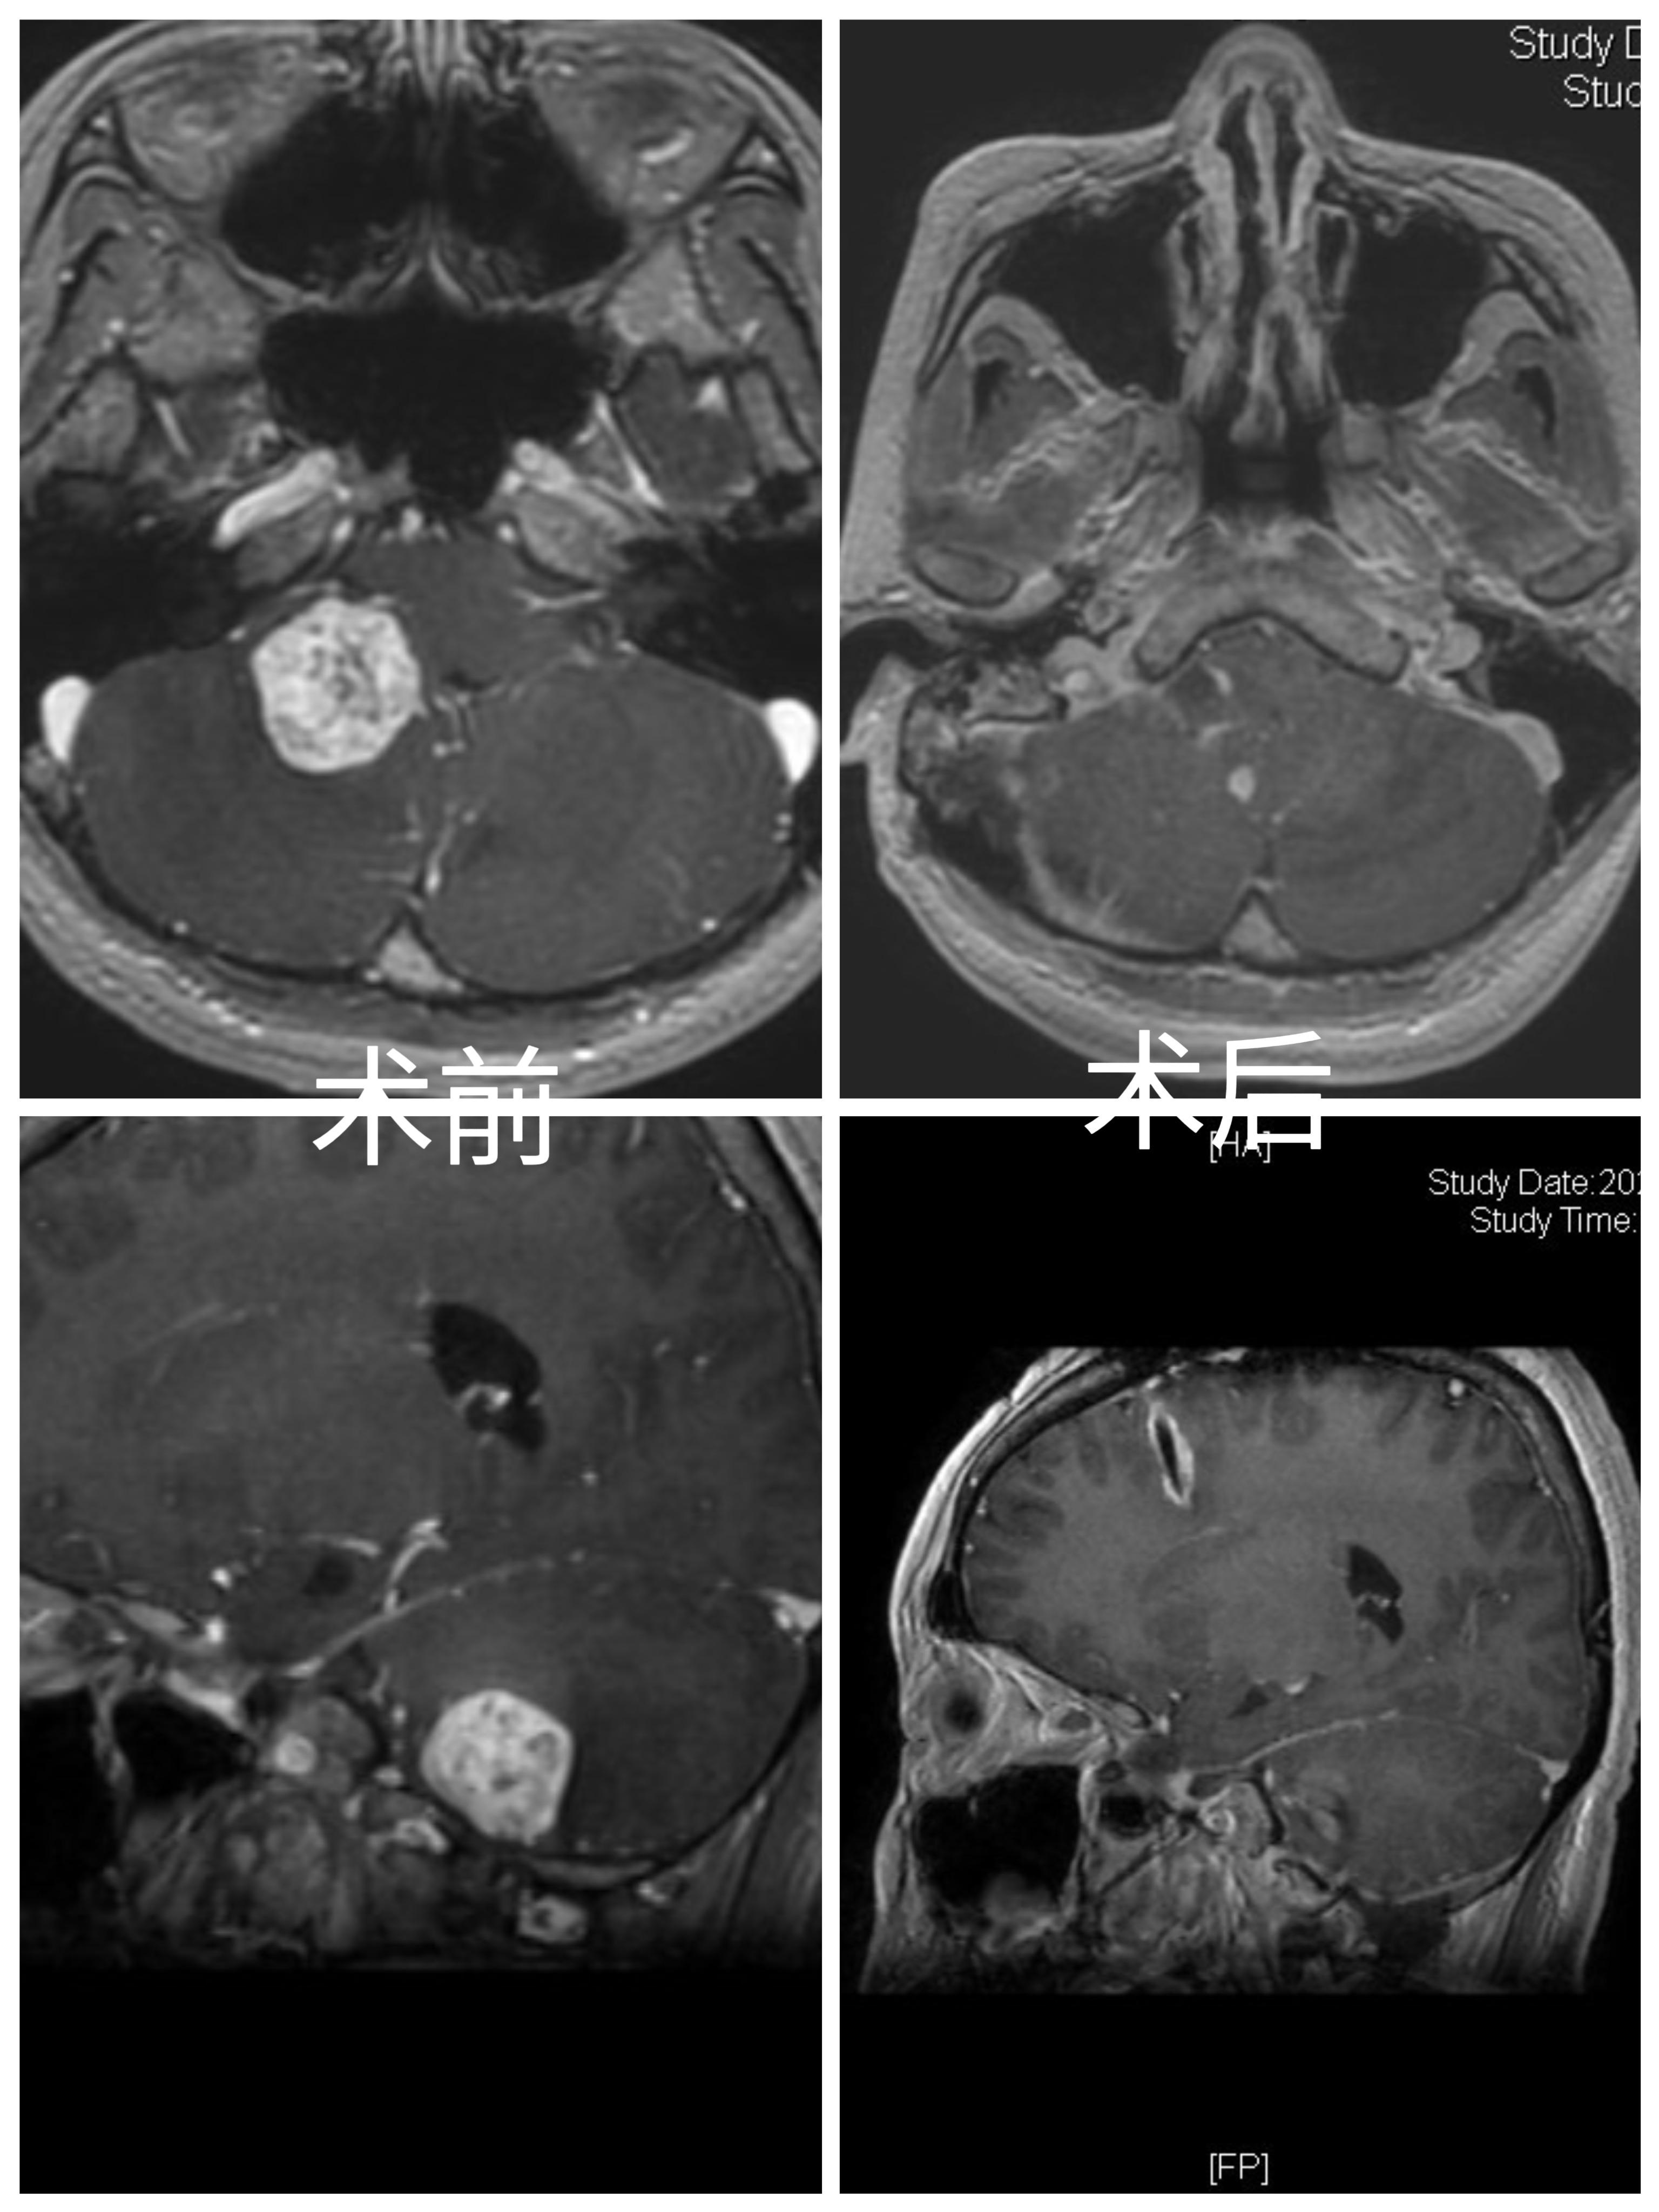

手术要点:

1.开颅前侧脑室外引流。

2.乳突后切口,延长至寰椎水平。

3.骨窗显露乙状窦,打开枕大孔外侧缘。

4.在小脑半球及小脑扁桃体外侧,切开脑组织,即见红色肿瘤。

5.沿肿瘤边缘分离,电凝切断血供,保护粗大引流静脉。

6.术中见肿瘤供血动脉,主要来源于小脑后下动脉的延髓外侧段、延髓近四脑室侧孔处动脉。

7.弱电凝延髓外侧细小血管,保护延髓正常血管。

8.临时阻断PICA,肿瘤血供明显减少。因肿瘤位于狭小空间,整体切除容易造成延髓损伤,而且不易电凝供血动脉。分块切除肿瘤,电凝切断延髓外侧段PICA,同时保护延髓及PICA。

9.严格沿边缘切除肿瘤,延髓表面静脉压迫止血。

10.术后病人轻度声音嘶哑、饮水呛咳。肢体活动正常。

Surgical points:

1. Preoperative external ventricular drainage on the lateral side of the brain.

2. mastoid incision, extended to the level of the atlas.

3. expose the sigmoid sinus through the bone window, and open the lateral edge of the foramen magnum.

4. On the lateral side of the cerebellar hemisphere and cerebellar tonsil, cut the brain tissue to reveal the tumor.

5. Separate along the edge of the tumor, coagulate and cut off the blood supply, and protect the large drainage veins.

6. During the operation, it was found that the feeding arteries of the tumor mainly originated from the lateral segment of the PICA ,near the foramen of the fourth ventricle of the medulla oblongata.

7. Weak coagulation of the small vessels on the lateral side of the medulla oblongata to protect the normal vessels of the medulla oblongata.

8. Temporarily block the PICA, and the blood supply of the tumor is significantly reduced. Due to the tumor located in a narrow space, it is difficult to remove the tumor as a whole ,and it is easy to damage the medulla oblongata. The tumor is removed in pieces, and the PICA on the lateral segment of the medulla oblongata is coagulated and cut off while protecting the medulla oblongata and PICA.

9. Strictly remove the tumor along the edge, and compress and stop bleeding on the surface of the medulla oblongata.

10. After the operation, the patient had mild hoarseness and drinking choking. The limb activity was normal.